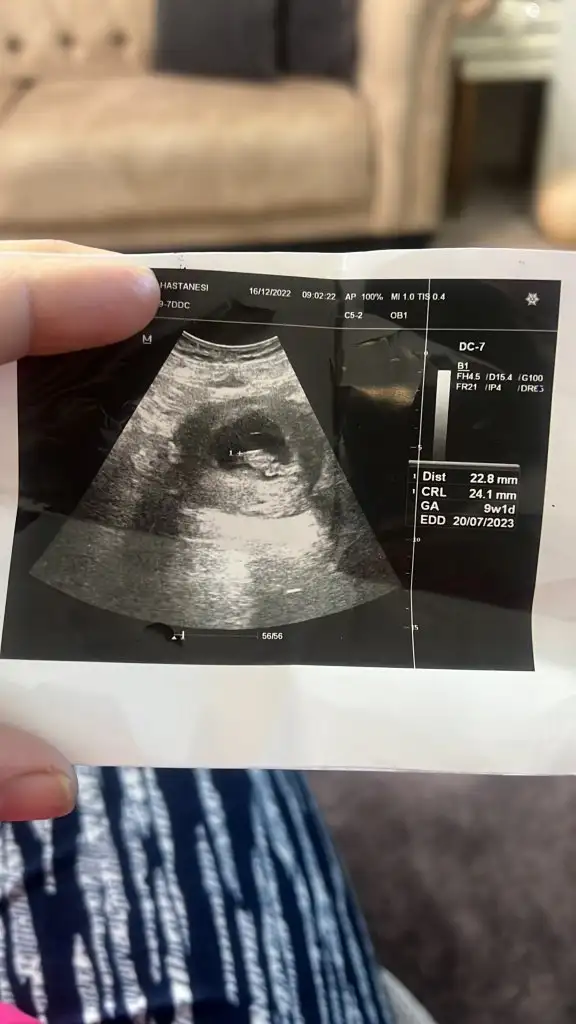

Cinsiyettt tahmini🥰❤️lütfennnnn

Merhabalar bende ultrason görüntüsünü yüklesem tahmin de bulunabilir misiniz çok heyecanlıyım

13 haftalik ti benim kemik yapisindan kıza benziyor dedi cin takvimi erkek yazıyor kemik yapisinda belli oluyor mu ya cinsiyet

Evet kemik yapisindan anliyor doktorlar. Kiza benziyor dediyse yuzde 89,90 kizdir. Ben de 11 haftalikken doktorum 2 hafta onden gidiyordu kizim, kesinlikle kiz dedi. Yanilmadi da, kemik yapisindan anliyorlar